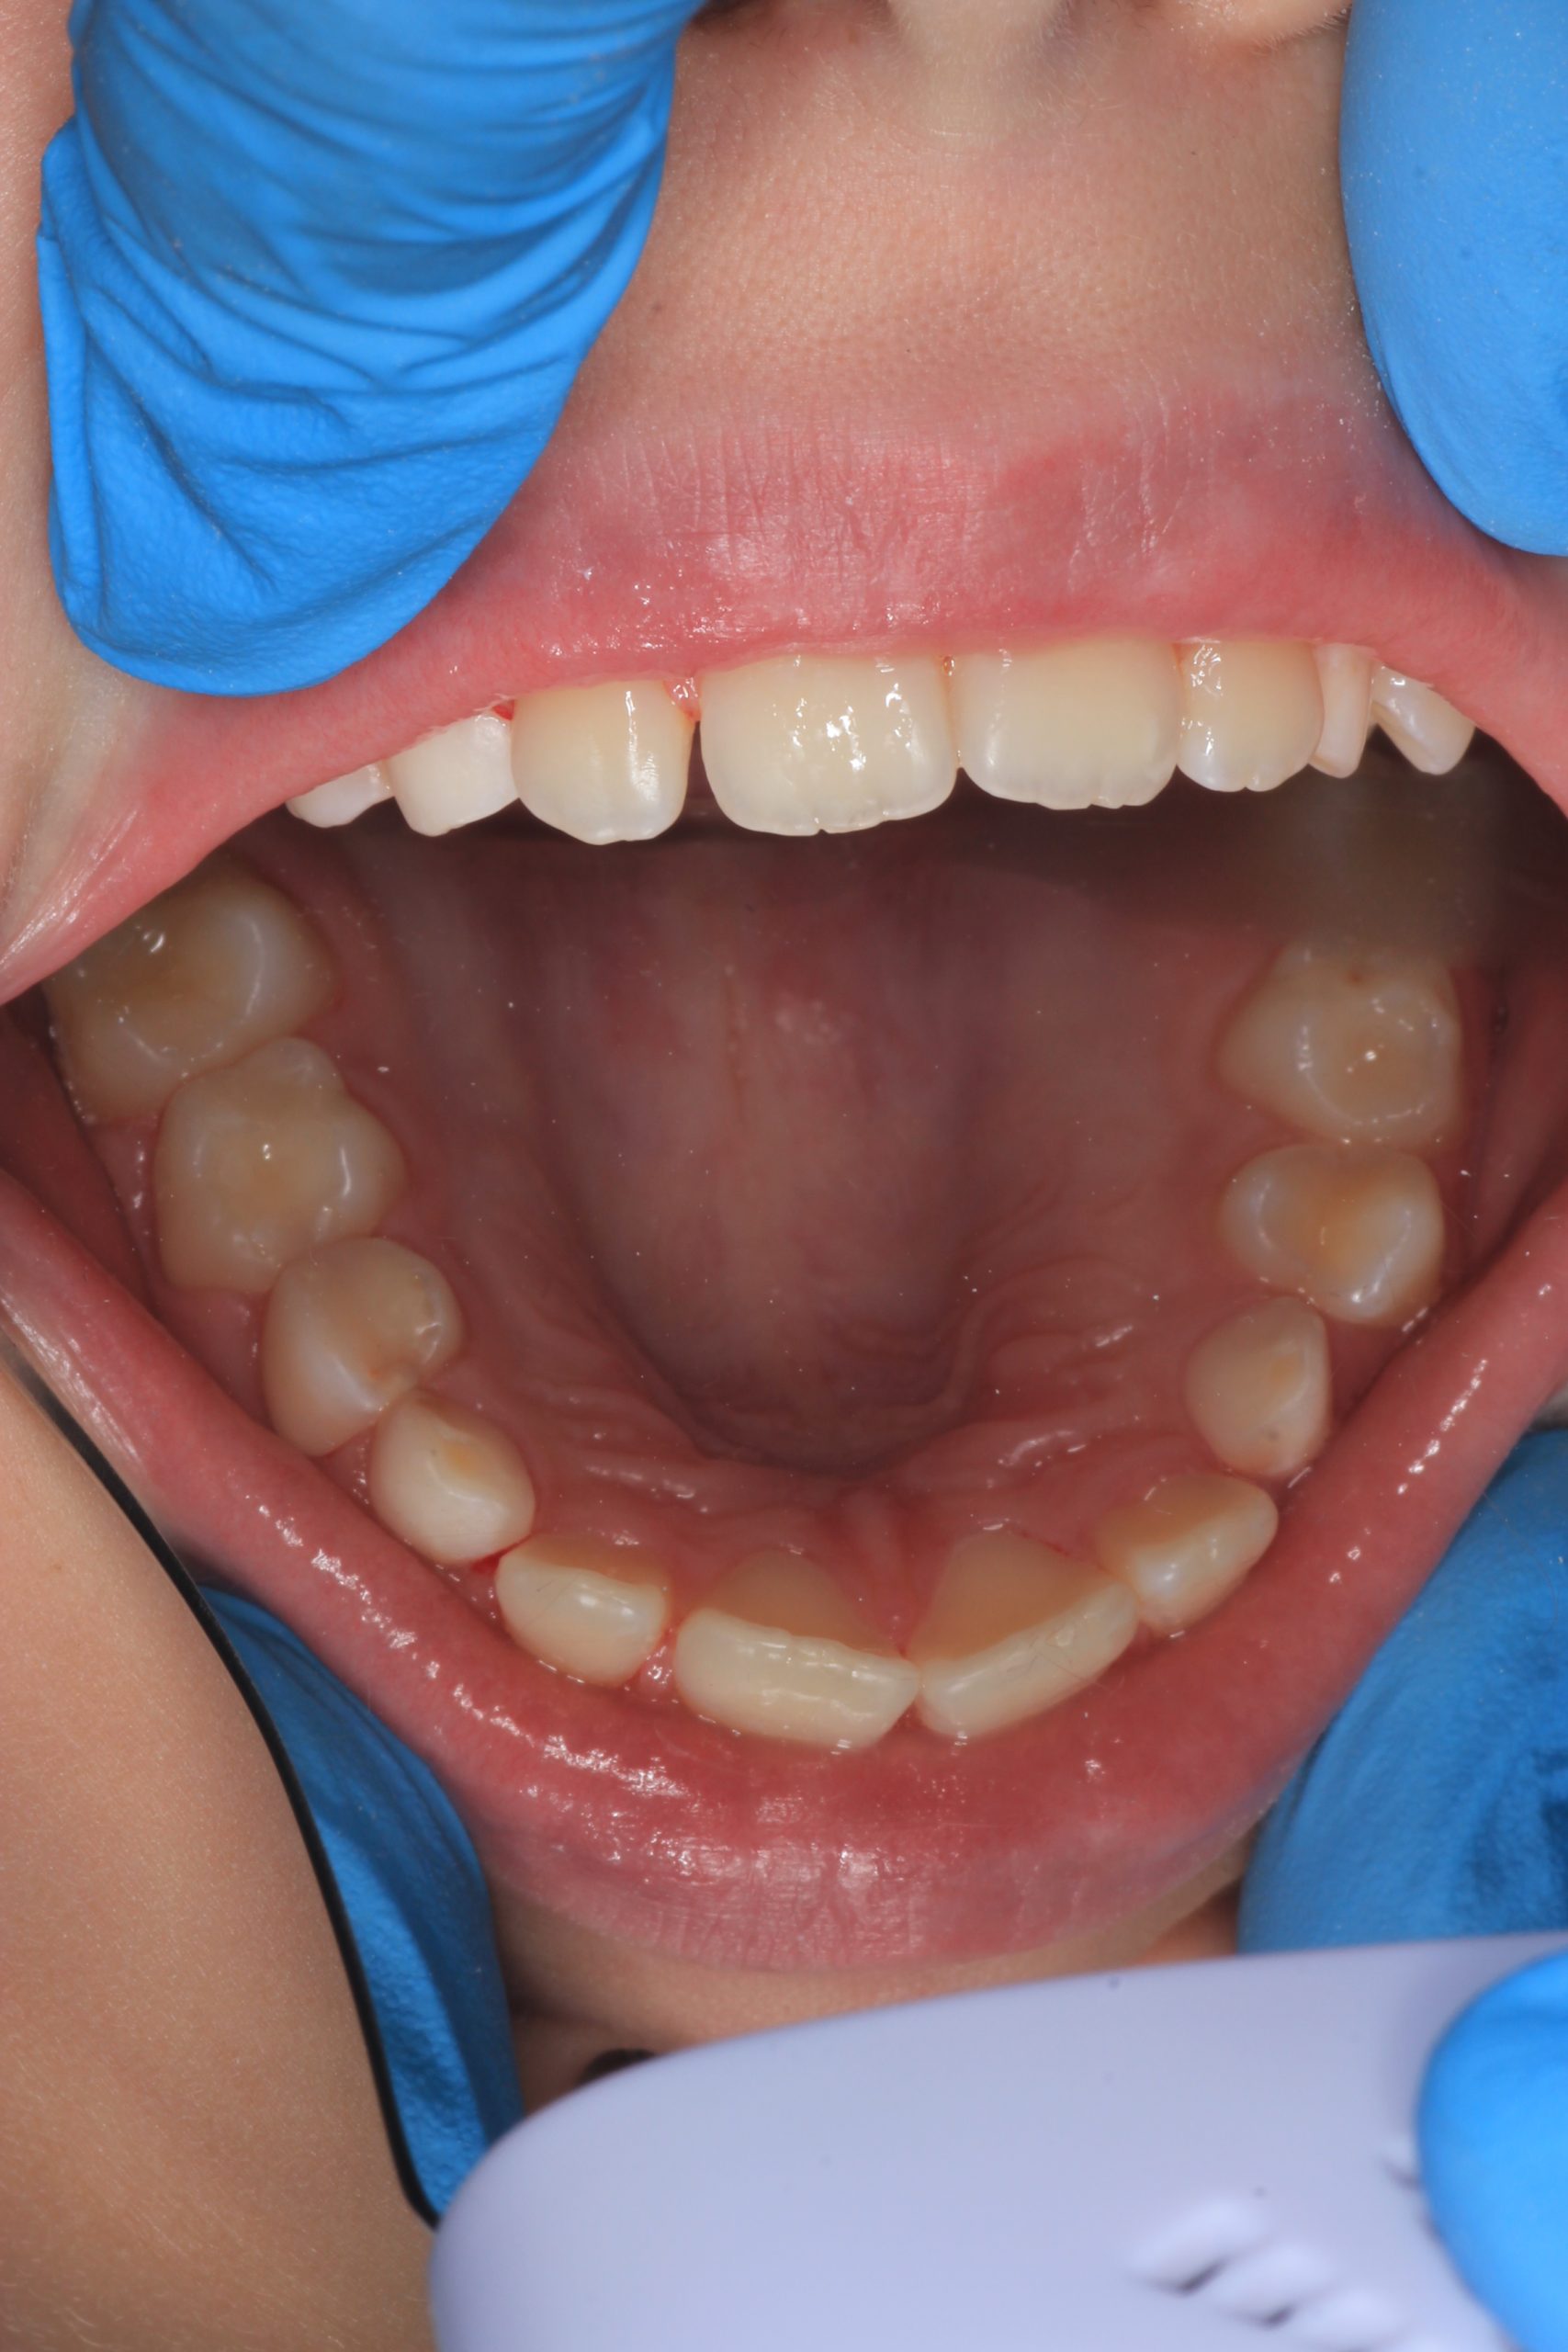

- Detailed Examination

We examine the condition of teeth, gums, and bite. - Plaque Disclosure with Special Indicators

Areas that weren’t cleaned well appear purple. The darker the shade, the older the plaque. This helps both kids and parents understand where brushing needs to improve. - Brushing Training & Home Care Tools Selection